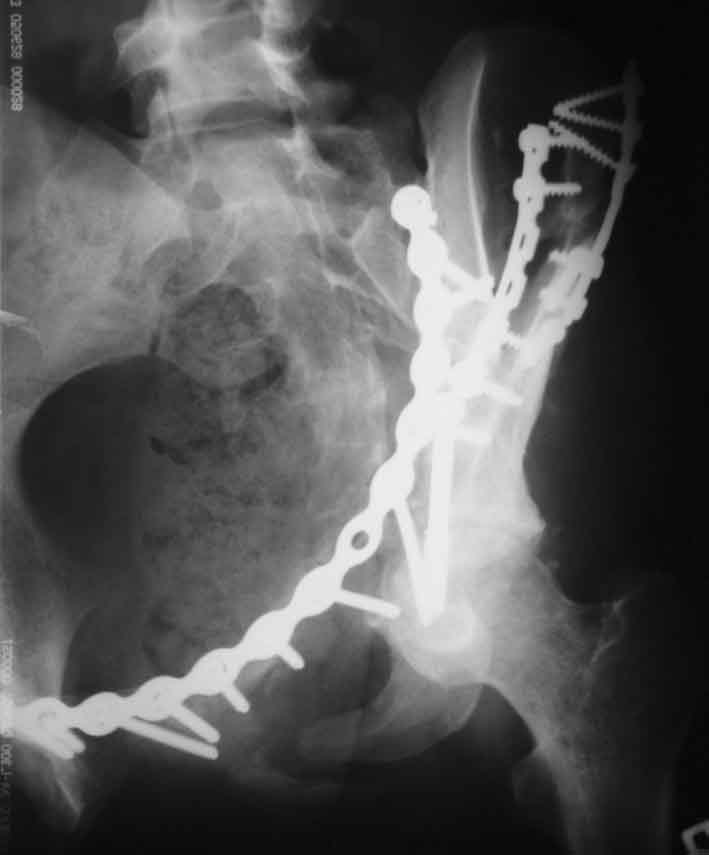

Рентгенограмма после операции. Изв. за качество. На днях переделаем.

Прямая проекция

inlet

подвздошная

запирательная

По всей видимости, вы имеете в виду канюлированный винт, который проецируется на вертлужной впадине. Та вот, он проведен не через лонную, а седалищную кость. Вертлужная впадина абсолютно интактна. Это хорошо видно на проекции inlet.